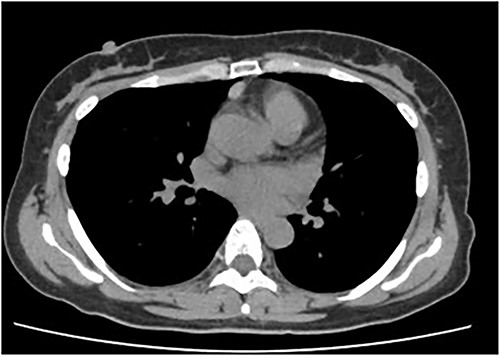

An asymptomatic 42-year-old female, with a history of ulcerative colitis and posterior longitudinal ligament ossification, had a mediastinal tumor detected incidentally on magnetic resonance imaging (MRI) and was admitted to our hospital for surgical intervention. No findings such as ptosis or muscle weakness were observed. Chest non-contrast computed tomography (CT) scans showed a well-circumscribed tumor shadow with a diameter of 18 mm in the anterior mediastinum (Fig. 1). Thoracic MRI revealed a homogeneous tumor with iso-intensity on T1-weighted and low-intensity on T2-weighted imaging. The tumor markers alpha-Fetoprotein, human chorionic gonadotropin, and carcinoembryonic antigen were within normal ranges. Serum anti-acetylcholine receptor antibody levels were normal. The patient underwent partial thoracoscopic thymectomy. The tumor, located at the edge of the right lower pole of the thymus, was smooth, slightly solid, and covered with mediastinal pleura. The pale red color of the tumor was visible from the surface through the pleura, indicating that it was located in superficial layer close to the pleura (Fig. 2). The tumor was resected along with the surrounding thymus with a sufficient resection margin. Gross examination revealed an 18 × 15 mm lobular whitish solid tumor below the pleura (Fig. 3A). Microscopic examination revealed that the tumor was composed of epithelial-like cells with significant lymphocytic infiltration and was divided into several lobules by fibrous septa. However, mitosis was rarely observed (Fig. 3B). The formation of the fibrous capsule was incomplete, and intermittent fibrous tissue was observed around the tumor (Fig. 3C). The surgical margins were negative. The tumor was pathologically diagnosed as a type B1 thymoma [World Health Organization (World Health Organization: WHO) classification], T1aN0M0, Stage I (TNM classification 8th edn), and Stage II, according to Masaoka–Koga staging. The patient was discharged on postoperative Day 7 without any complications. As curative resection was achieved, adjuvant therapy was not planned. Our patient has been followed up for 18 months postoperatively, with no recurrence.

Chest CT showing a well-circumscribed tumor shadow of 15 mm in the anterior mediastinum.